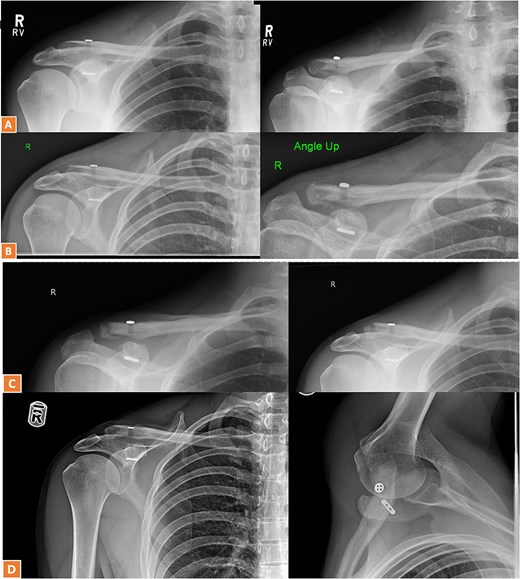

A 27-year-old male suffered a right lateral clavicle fracture after a fall (Fig. 5). He underwent TightRope fixation with stabilization of the coracoclavicular ligament. Rehabilitation was initiated early, and by three months, he had full shoulder motion and returned to overhead sports. Radiographs confirmed union, and the patient reported minor scar sensitivity and transient keloid formation, with no functional limitations (Fig. 6A–D).

Radiographs of third case showing a displaced lateral clavicle fracture with deformity.